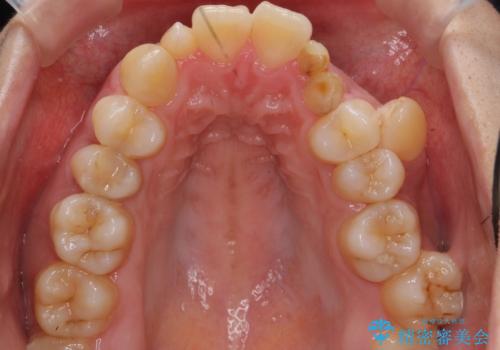

- 歯並びを気にして来院。

乳歯が残存しており、また左上の犬歯もずれて生えてきていました。

右上の前歯も細長い特殊な形をしていました。(矮小歯といいます)

左上の奥歯はすれ違っていたためそのかみ合わせも整えています。